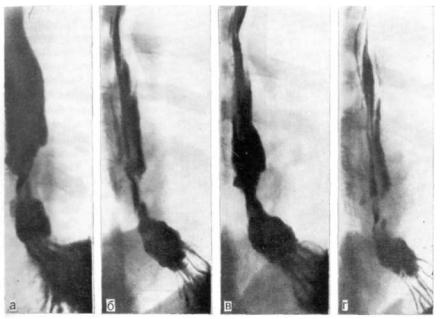

Современные технологии в медицине: рентгенодиагностика заболеваний желудка

Раздел: Фотогалерея мыслей